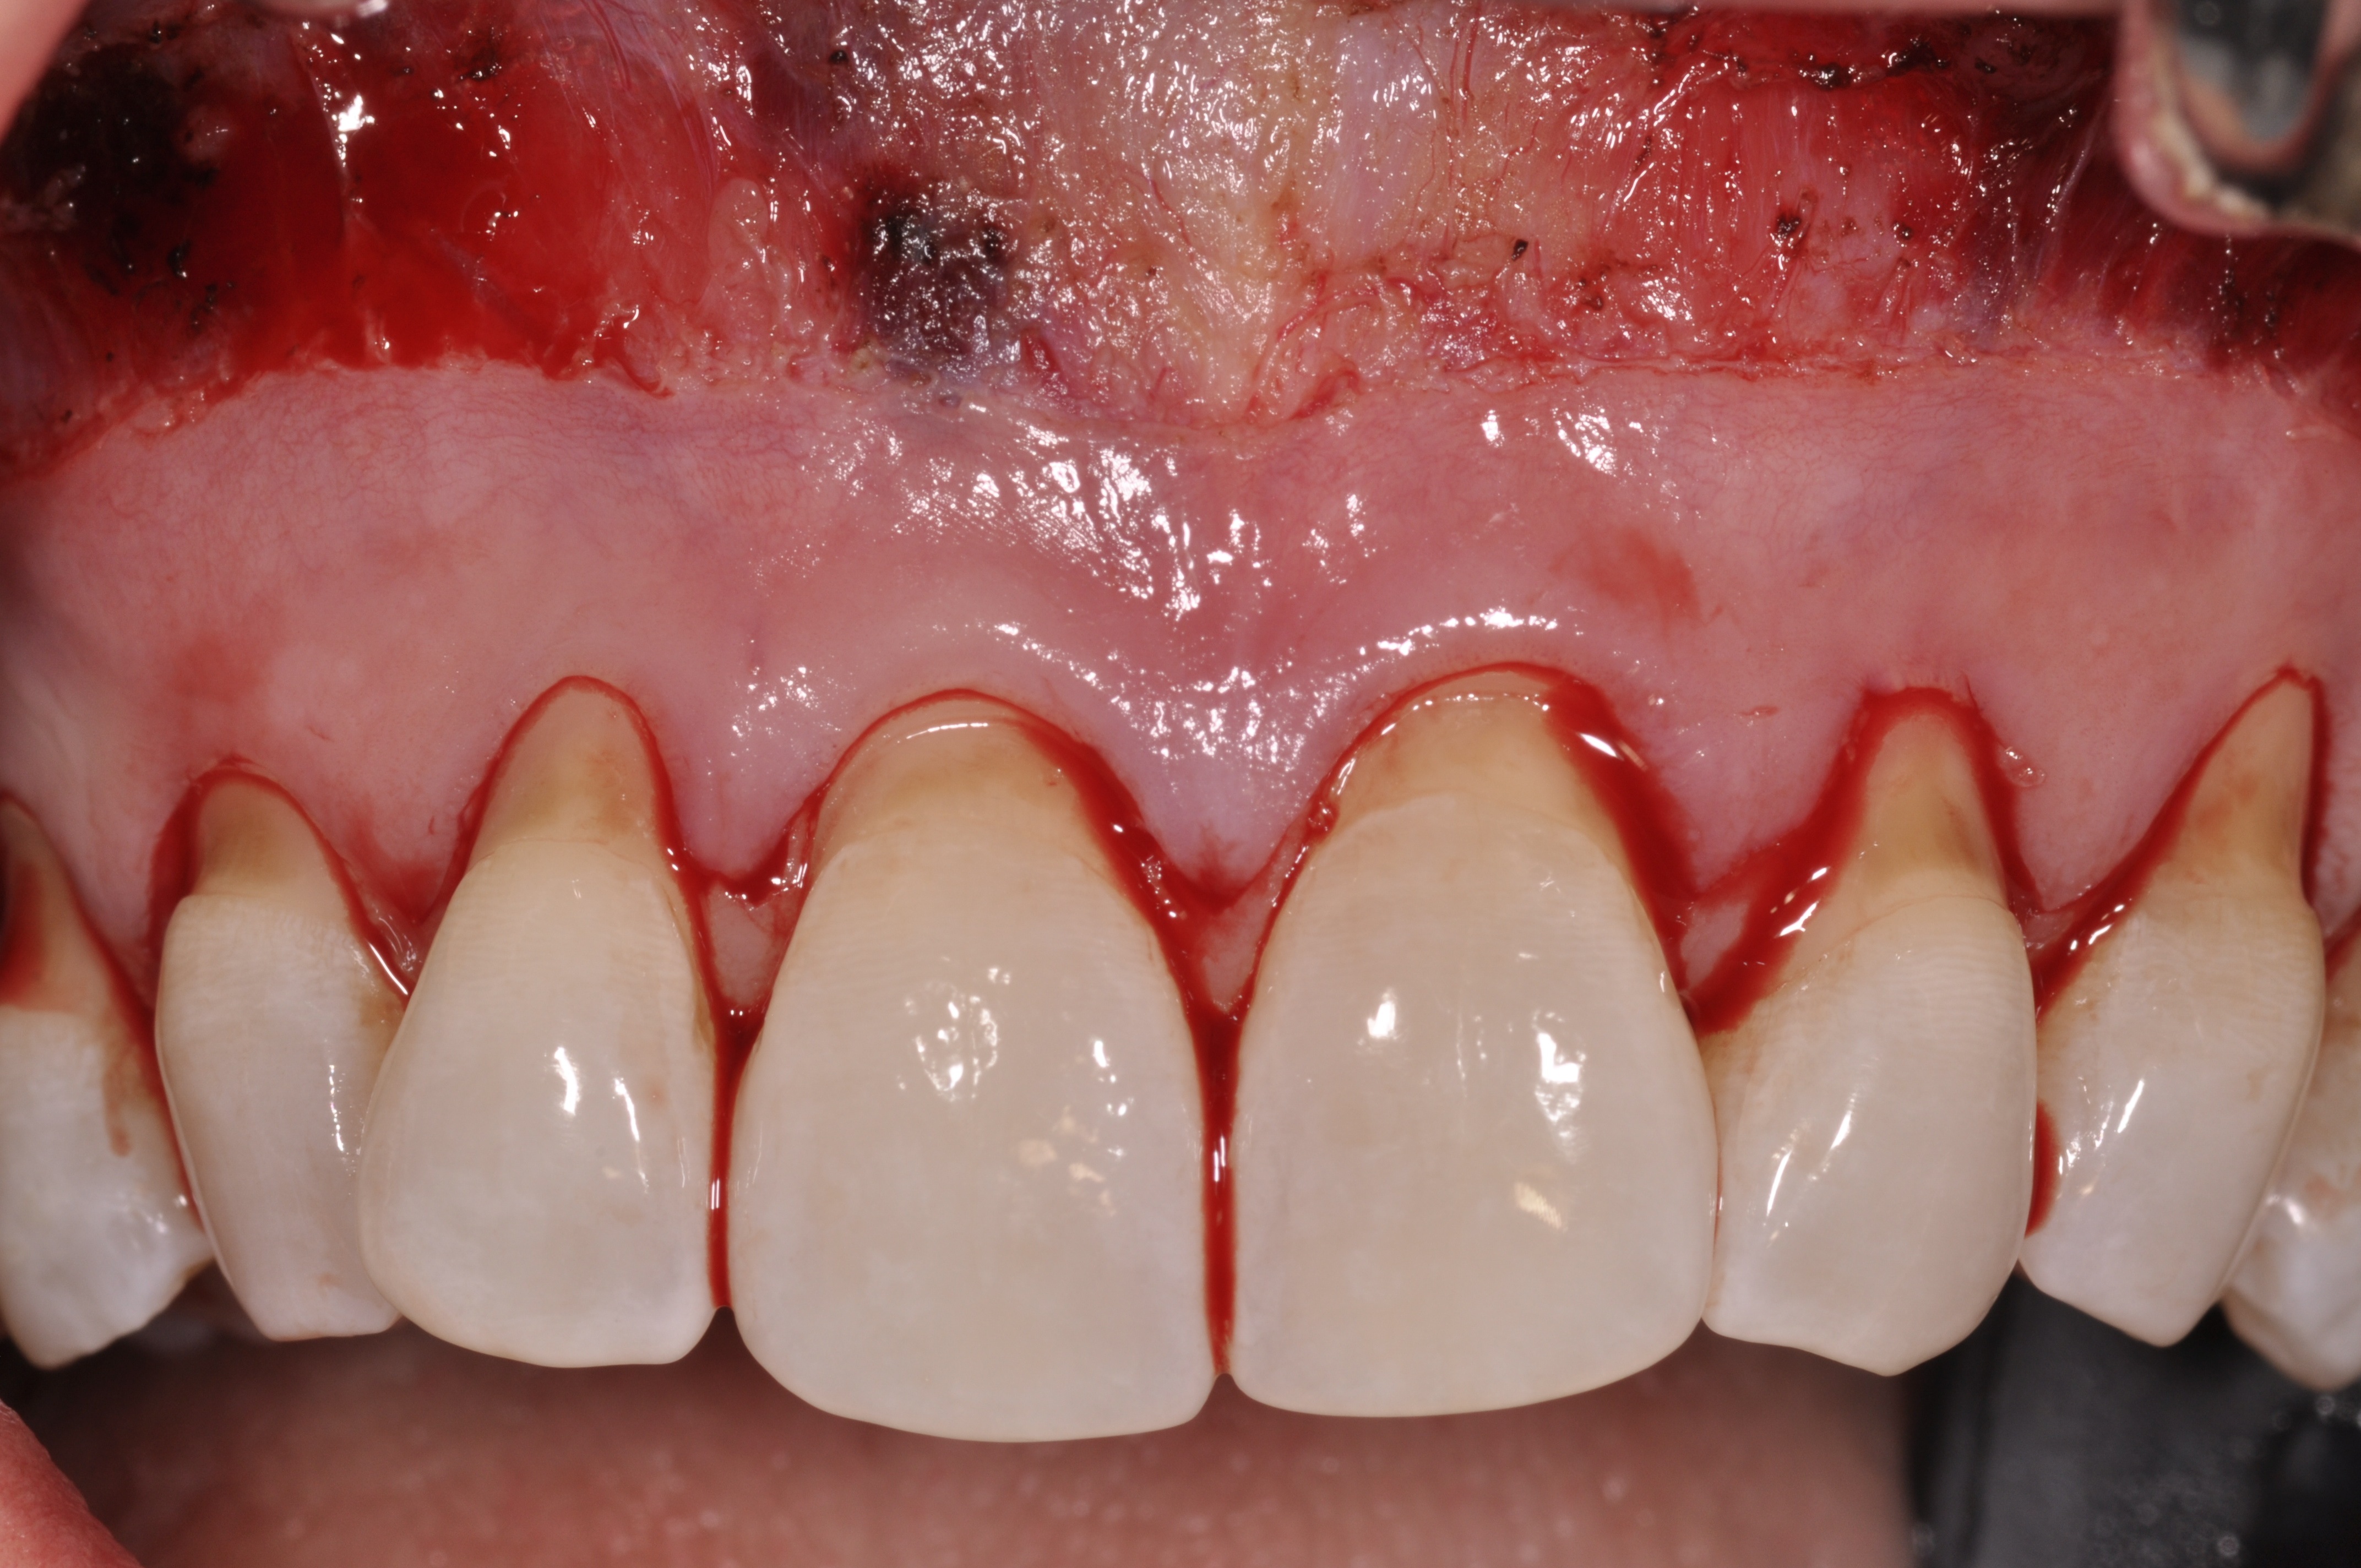

After initial incision techniques were done, a papillary-sparing incision was performed, leaving the crest of the papilla intact (Figure 10), thus allowing flap closure to be accomplished with a bed of autogenous tissue to support revascularization of the dermis/buccal flap complex. A full-thickness flap was then elevated to the mucogingival junction, after which a split-thickness dissection with a blunt elevator superior to the mucogingival junction area was performed to allow for release of tension and to let the buccal flap be mobilized coronally at closure (Figure 10). Care must be taken to avoid perforating the tissue in the region of the vestibuloplasty incision. After tension-free release of the flap, root planing of the exposed root surfaces was accomplished, followed by removal of the smear layer of cementum and chemical detoxification with a citric acid solution pH1 applied over the previously root-planed surfaces. After root preparation, the keratinized papillary tissues that remained following initial incisions were de-keratinized by using a #4 round diamond on a high-speed handpiece. De-keratinization provided a wound bed that enabled the dermal matrix graft to be secured and supported revascularization of the coronally repositioned buccal flap at closure.

Fig 10. Initial incisions, and blunt, split-thickness dissection for tension-free closure.

Figure 10